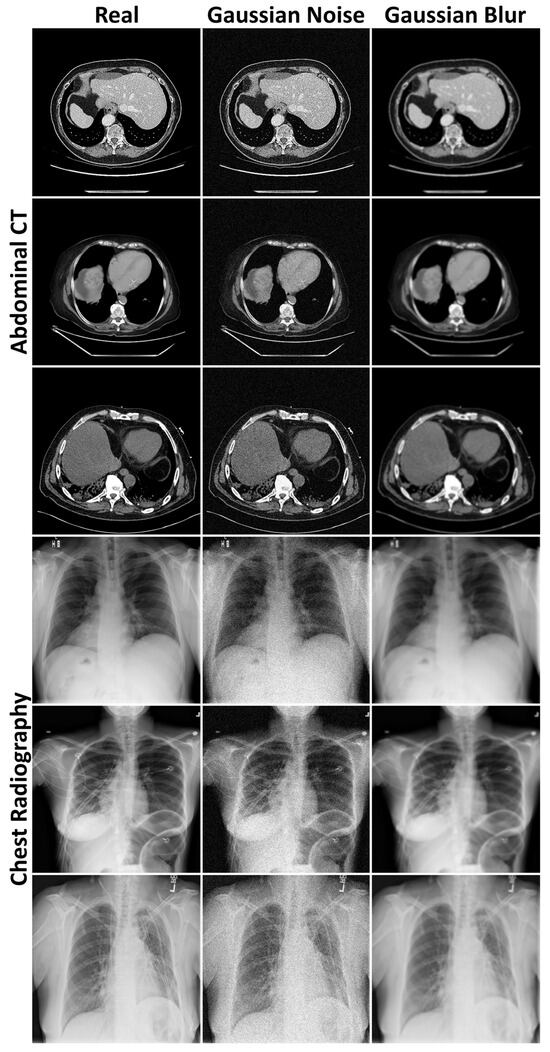

3.1. Evaluation of Generated Image Quality